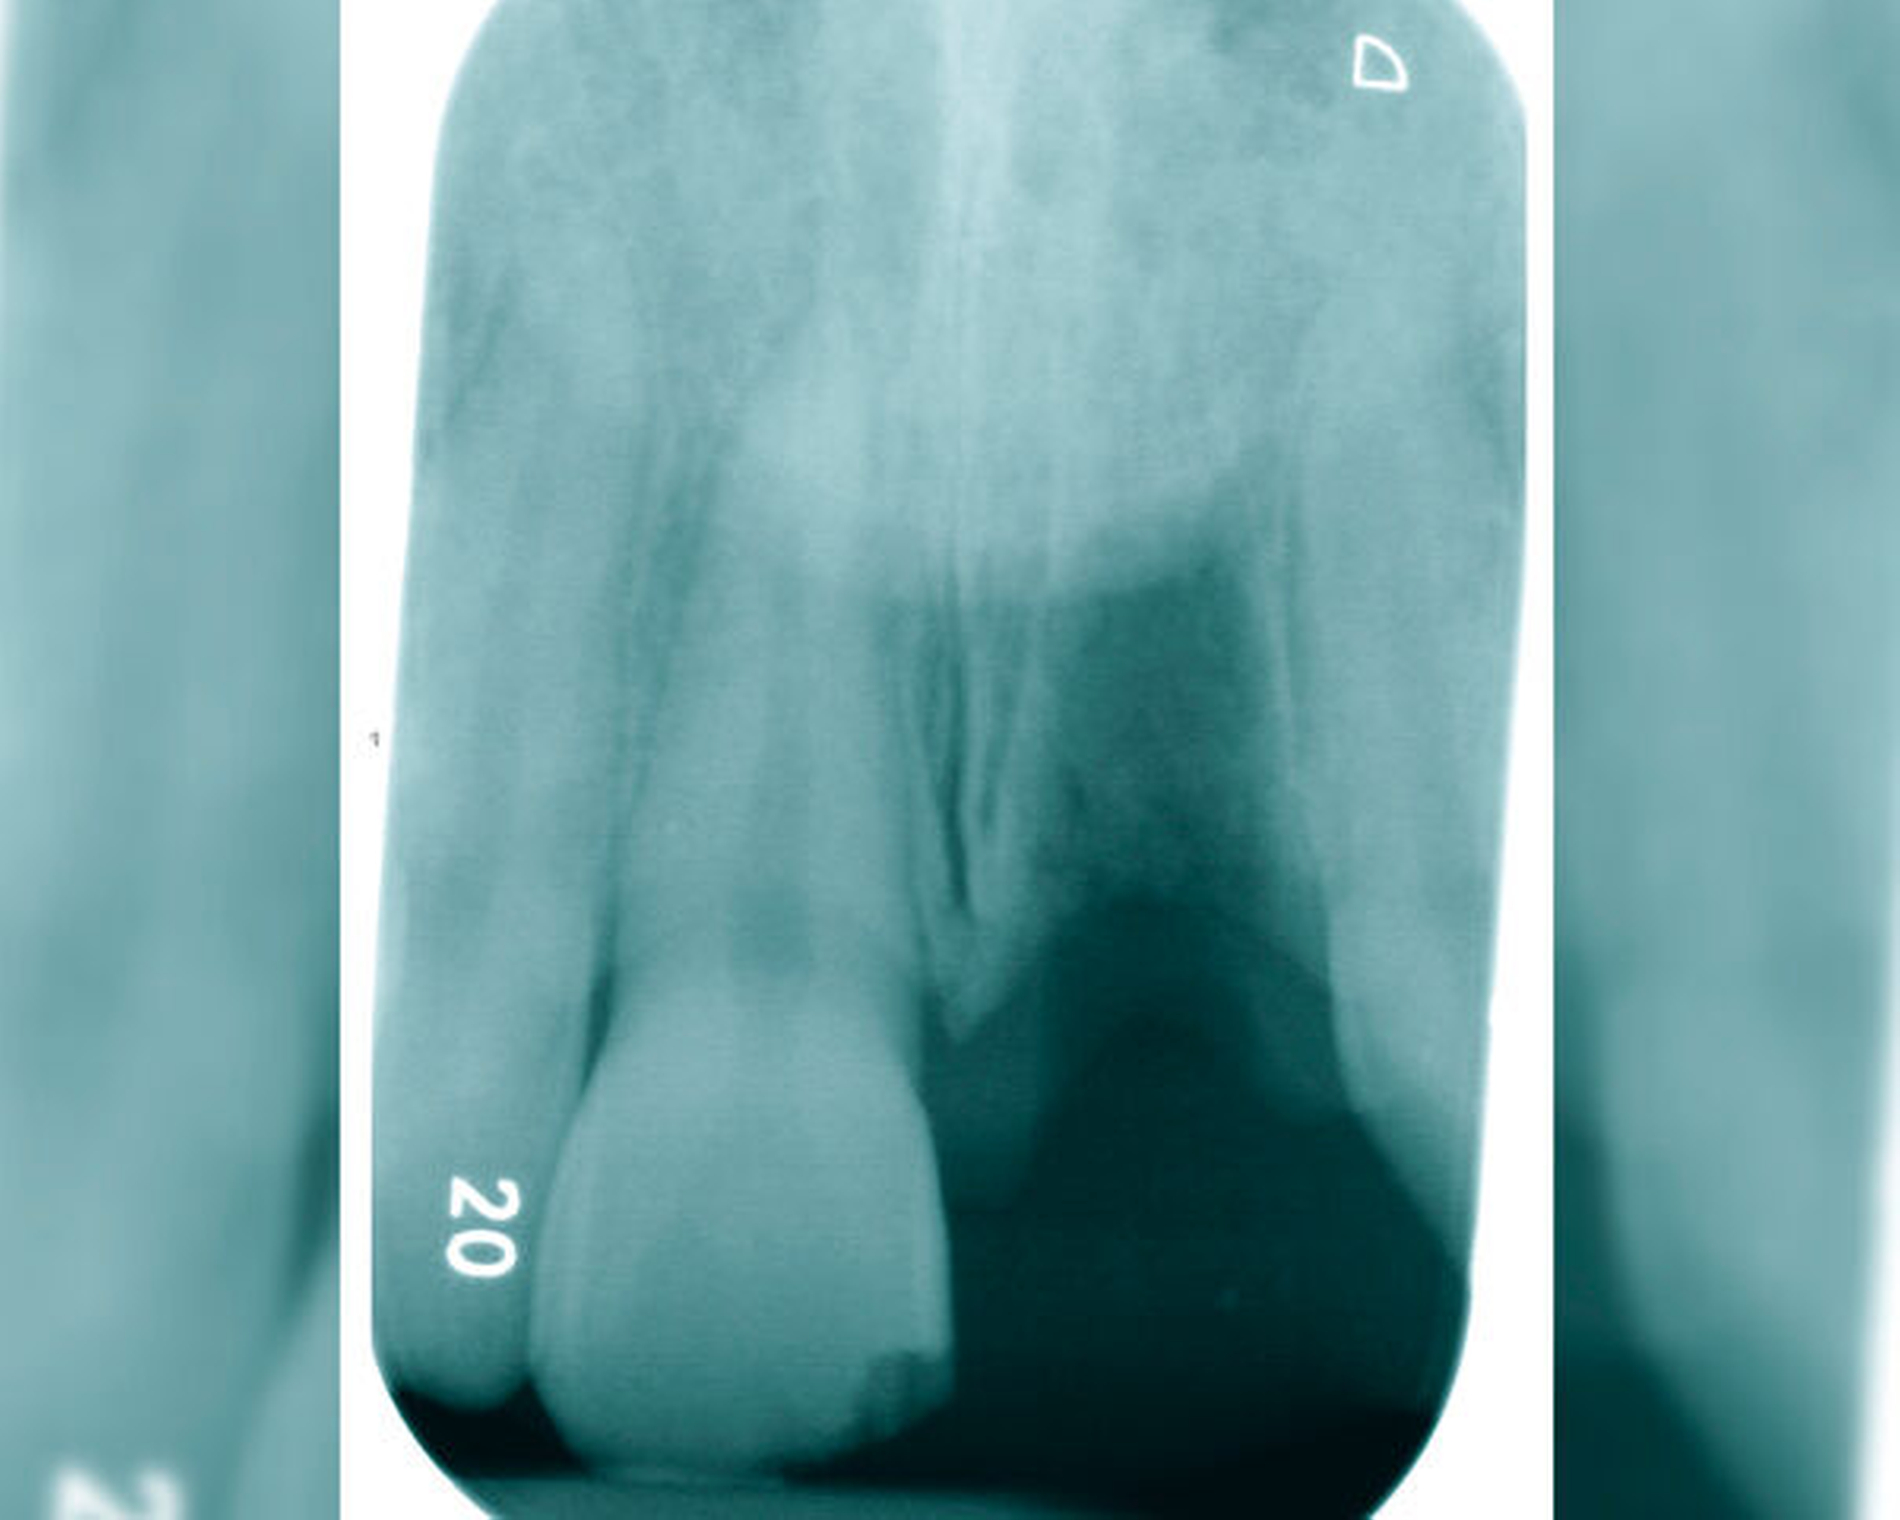

„Ubi pus, ibi evacua!“ – der lateinische Aphorismus wird häufig in vielen Bereichen der Medizin zitiert. Dieser Grundsatz trifft auch auf die Behandlung von akuten apikalen Abszessen zu. Der erste Weg der Behandlung sollte hier, wann immer möglich, über den Wurzelkanal gehen, um eine Drainage für den Pusabfluss zu schaffen (Abbildungen 1 und 2). Das nekrotische Pulpagewebe oder die bereits vorhandene Wurzelkanalfüllung gilt es von orthograd zu entfernen. Die Wurzelkanalpräparation kann die Drainage des Abszesses weiter unterstützen. Mittels der chemischen Desinfektion im Zuge eines suffizienten Spülprotokolls erfolgt eine weitere Elimination von Mikroorganismen und nekrotischem Pulpagewebe aus dem Wurzelkanallumen. Zur weiteren Desinfektion und zur Anhebung des pH-Wertes wird eine wässrige Kalziumhydroxideinlage in den Wurzelkanal eingebracht. Ein „Offenlassen“ des Zahnes nach der Schmerzbehandlung gilt es zu vermeiden, da sich Mikroorganismen aus der Mundhöhle im Wurzelkanal ansiedeln und nachfolgend zu einem Biofilm kolonialisieren können [Siren et al., 1997]. Lässt sich der Pusabfluss aus dem Wurzelkanal nicht stoppen, kann ein Zahn in Ausnahmefällen für maximal 24 Stunden offengelassen, am folgenden Tag in der Praxis endodontisch versorgt und mit einem provisorischen Verschluss versehen werden [Schäfer et al., 2021].

Symptomatische irreversible Pulpitis (Abbildung 3)